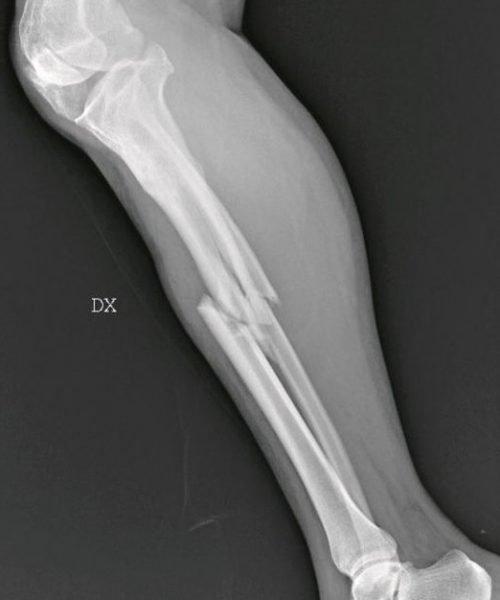

Σοκάρουν οι ακτινογραφίες από περιστατικά επιθέσεων κατά γυναικών - Εγκαύματα, μελανιές, σπασμένα οστά, σημάδια στραγγαλισμού, μαχαίρι στην πλάτη

Με αφορμή την Ημέρα, η ιταλική «La Repubblica» φιλοξένησε την γιατρό Μαρία Γκαρσία Βανταντόρι σε ένα εξαιρετικό αφιέρωμα το οποίο δημοσίευσε ακτινογραφίες γυναικών που έχουν πέσει θύματα ενδοοικογενιακής βίας.

Η Μαρία Γκράτσια Βανταντόρι είναι χειρουργός επί 26 χρόνια στο μιλανέζικο νοσοκομείο Σαν Κάρλο. Με πρωτοβουλία της πραγματοποιείται μια έκθεση ακτινογραφιών κακοποιημένων γυναικών.

Η ίδια αναφέρει πως στις ακτινογραφίες των θυμάτων αντικατοπτρίζεται η καθημερινή φρίκη που αντιμετωπίζει με τους συναδέλφους της στα «Επείγοντα».

«Συχνά οι τραυματισμένες γυναίκες δεν έχουν τη δύναμη να πουν τι τους έχει συμβεί, αλλά τα σώματά τους και τα τραύματά τους μιλούν από μόνα τους», σημειώνει, μιλώντας στην ισπανική εφημερίδα.

Σύμφωνα με την ίδια, καθημερινά καλούνται να αντιμετωπίσουν «σπασμένα οστά σε μύτη, χέρια, πόδια, πληγές από μαχαιριές, εγκαύματα, μελανιές και άλλα σημάδια στραγγαλισμού».

«Όλα αυτά τα χρόνια έχω δει χιλιάδες ακτινογραφίες γυναικών με κάθε είδους τραύματα, ακόμη και πολύ σοβαρά. Πολλές από αυτές τις κακοποιημένες γυναίκες αρνήθηκαν ότι τα τραύματά τους προκλήθηκαν από τους συζύγους ή άλλα μέλη της οικογένειάς τους. Η άρνησή τους σχετίζεται με συναισθήματα όπως φόβος, ντροπή, αγωνία για την τύχη των παιδιών τους ή και για τη ζωή τους ακόμη», σημειώνει η γιατρός.